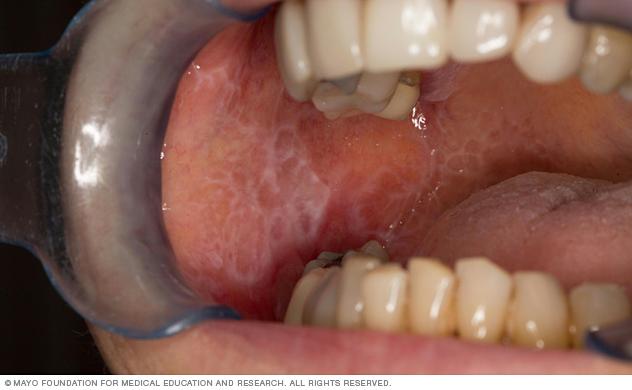

Oral lichen planus lesions cause lacy white patches in the mouth.

This white, lacelike patch on the interior surface of the cheek is typical for oral lichen planus.